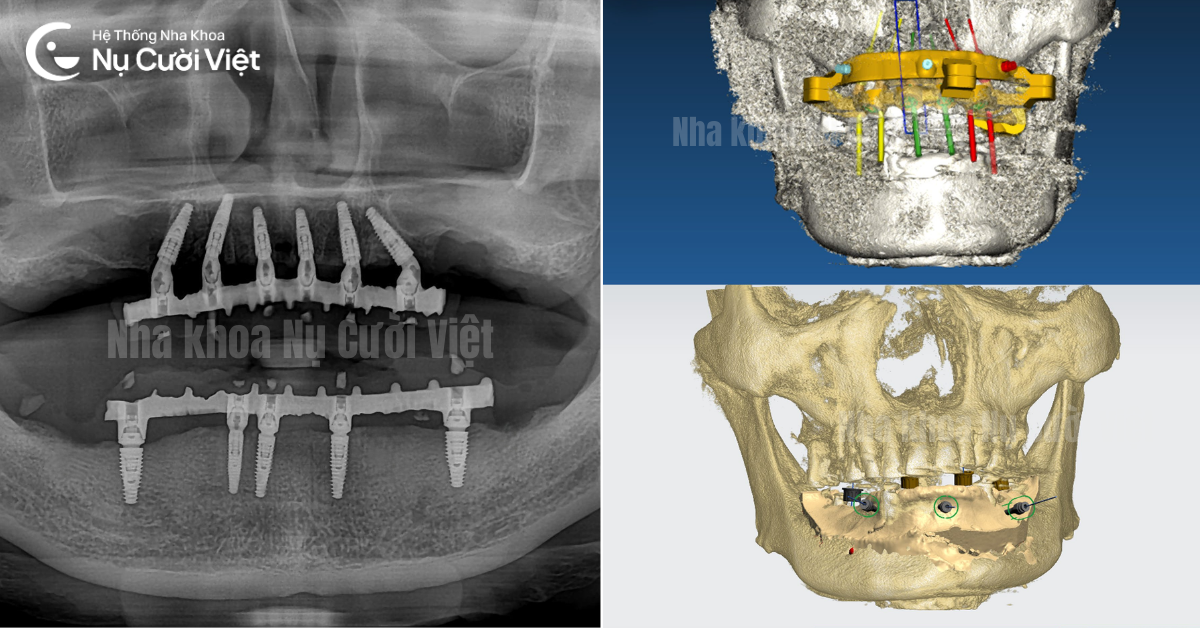

Máng hướng dẫn phẫu thuật Implant: Dựa trên dữ liệu phim CT Cone Beam, bác sĩ sẽ thiết kế một máng hướng dẫn chính xác đến từng milimet. Máng này giúp đặt trụ Implant vào vị trí lý tưởng mà không cần rạch lợi quá rộng, giúp vết thương nhỏ, ít chảy máu và hầu như không sưng.

Trồng răng Implant toàn hàm không đau với máng hướng dẫn phẫu thuật